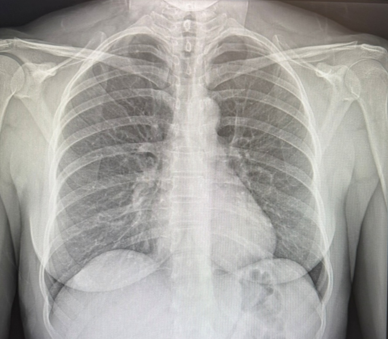

Chest X-ray (CXR)

Our staff performs digital chest X-rays efficiently and safely in our office.

Example of a digital chest X-ray used to evaluate the heart and lungs.

What Is an Chest X-ray (CXR)?

- A chest X-ray (CXR) is a fast, painless imaging test that creates a picture of the heart, lungs, and chest structures.

- It helps your medical team look for changes in heart size and shape, fluid buildup, and lung conditions that may affect breathing or place extra strain on the heart.

- A CXR can be useful when evaluating symptoms such as chest discomfort, shortness of breath, persistent cough, or swelling.

- It may also support the evaluation of conditions such as heart failure, fluid in the lungs (pulmonary congestion or pleural effusion), pneumonia, and other cardiopulmonary concerns.

What to expect

Our equipment is digital. The test usually takes only a few minutes. You will stand briefly while images are taken. The amount of radiation is extremely low, and the images are reviewed by our medical team as part of your overall cardiovascular assessment.